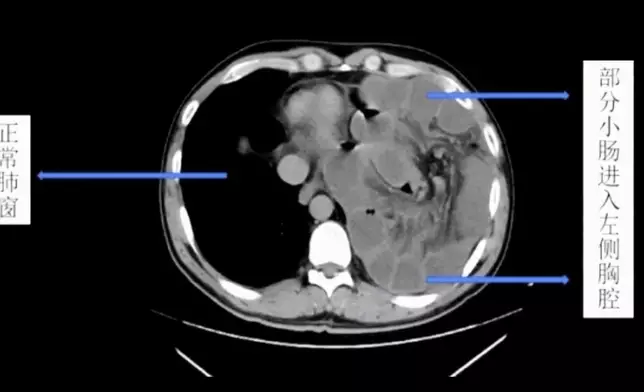

腹腔壓力突然升高或漸升就會造成膈肌破裂,破裂以後小腸就鑽進胸腔近2米。網上截圖

醫院腸胃外科主任邱磊表示:「病患是坐著輪椅來的,腹痛難忍,地方醫院已經替他打了兩隻強力的止痛藥,但疼痛仍無法緩解,到院時已經全身冰涼,雖然神智仍然清楚,但已經出現休克的徵兆,左肺的呼吸聲完全消失」,院方立刻替他進行電腦斷層掃描(CT Scan),「片子顯示左肺已經全都被壓縮扁了,左邊胸腔裡全都是白白的東西」,研判是男子的小腸。

邱磊表示,男子曾罹患結腸癌,當時手術切除掉部分的膈肌(diaphragm),「但修補的部位沒有天生的那麼堅固」,患者經常健身,加上愛喝酒常嘔吐,腹腔壓力變化大,造成膈肌破裂,「長達2米的小腸就從破裂的位置鑽進胸腔」,形成醫學上的「橫膈疝氣」(diaphragmatic hernia,膈疝)。

由於小腸的擠壓,男子左邊的肺已經被頂到嚴重萎縮,小腸堆積充血的結果也導致壞死與內出血,最後經過緊急手術切除,才脫離險境,但原本長約6米的小腸,只剩下約4米。